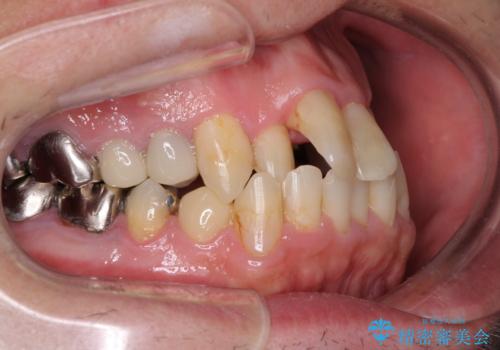

- 飛び出している上顎前歯と、奥歯に多くある銀歯を気にして来院された患者様です。

マウスピースで矯正を行いたい反面、一旦早めに前歯を整えたいというご希望があったため、まずは上顎前歯をワイヤー装置で整え、その後インビザラインにて仕上げていくこととしました。

矯正治療後には、奥歯の銀歯をすべてセラミックにて補綴治療することとしました。